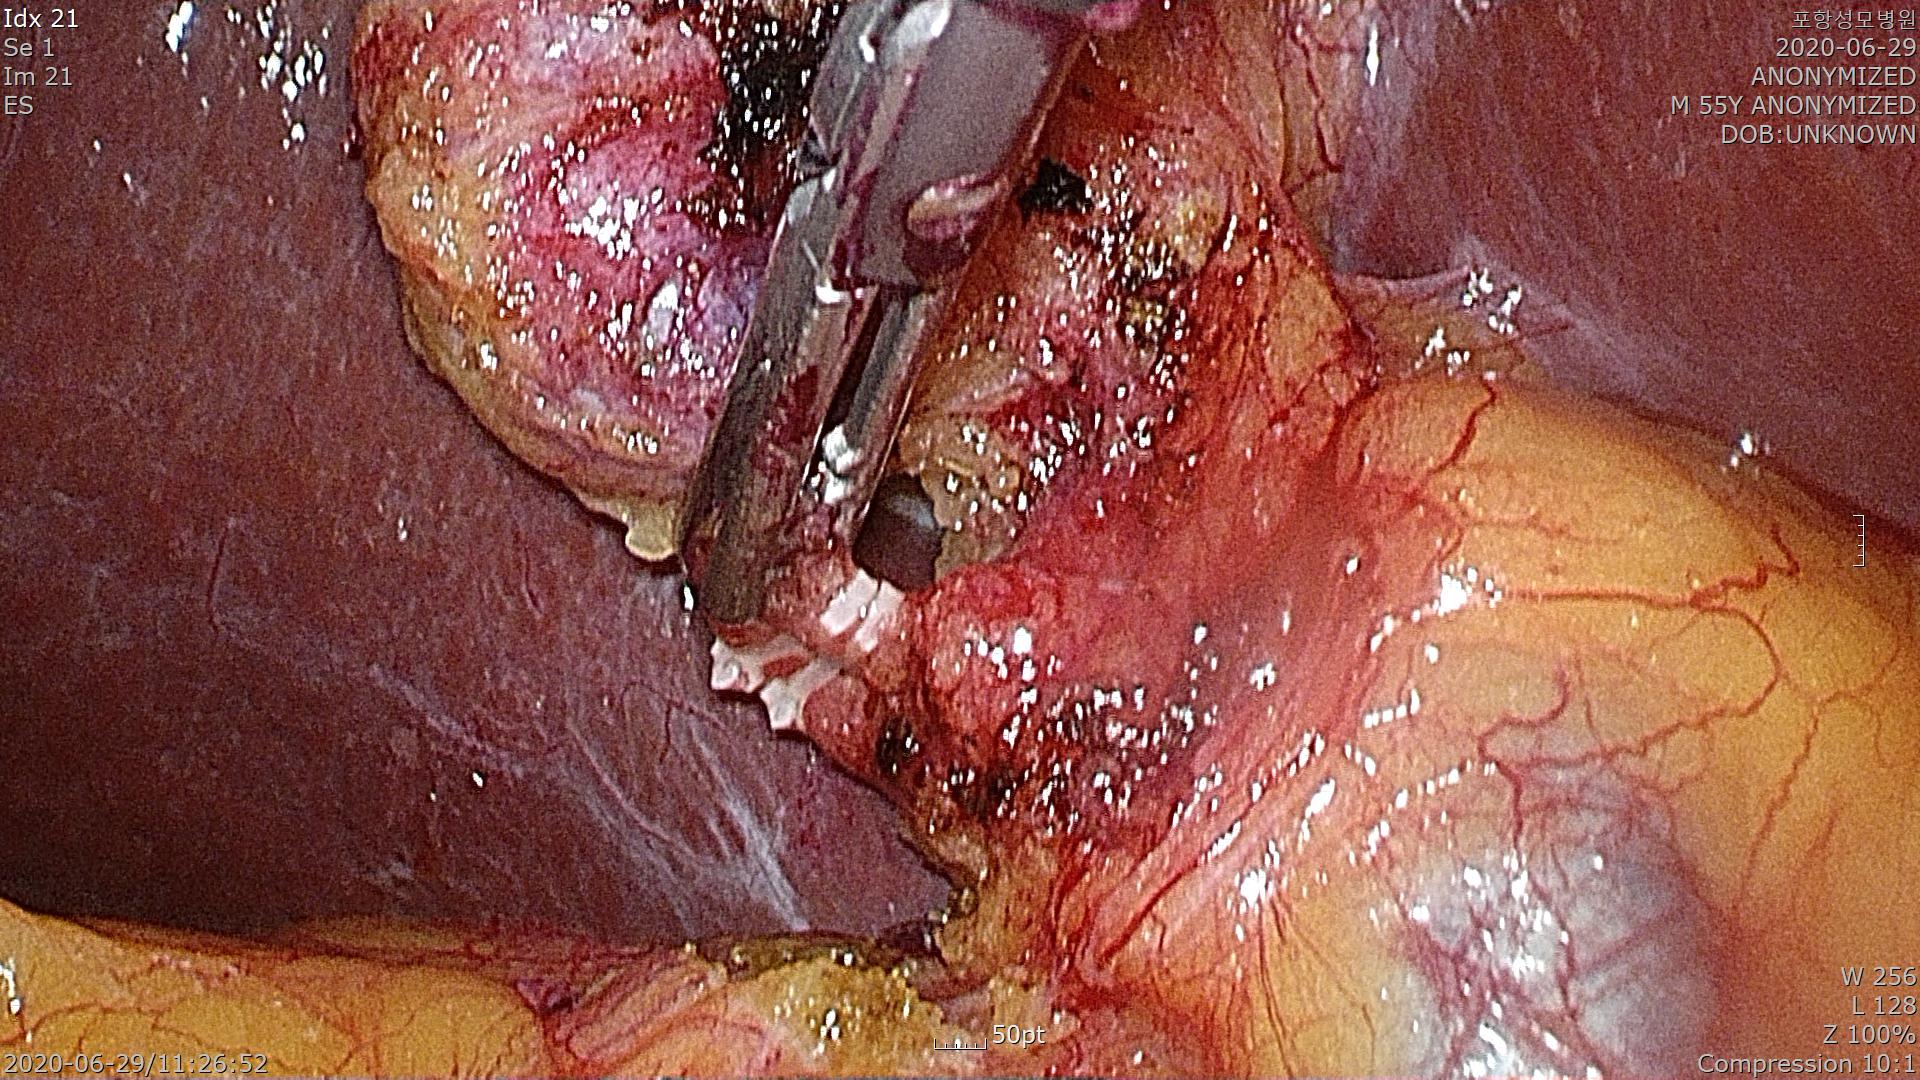

이제 복강내로 투관침을 다시 이동시켜 복강경 담낭절제술을 시작합니다.

담낭관(Cystic duct)를 결찰하는 장면입니다.

담낭동맥(Cystic artery)을 결찰하는 장면입니다.

간 후벽에 붙어있는 담낭을 간으로 부터 분리하고 있습니다.

총담관손상 및 출혈 없이 깨끗하게 잘 마쳤네요.